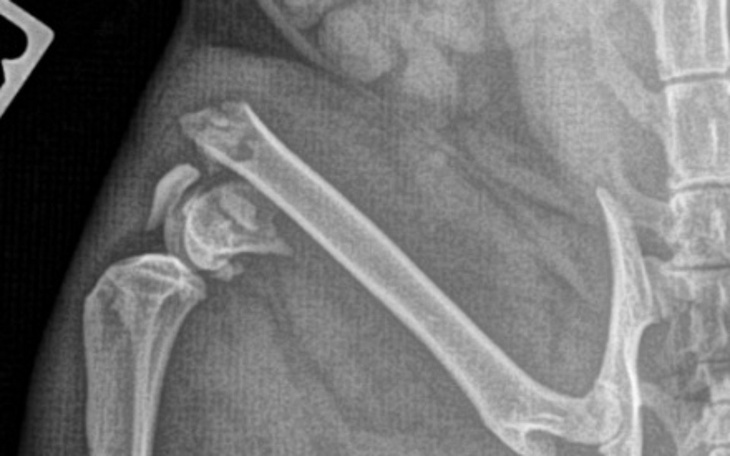

Okazało się że kot ma skomplikowane złamanie nasady kości udowej.

Potrzebna jest pilna operacja osteosyntezy , kot bardzo cierpi a Pana nie stać na zabieg bezdomnego kota, poprosił nas o pomoc.

Dr.Szałecki z lecznicy Cztery Łapy chce operować jak najszybciej.

Koszt operacji to minimum 2500zł. Rudego trzeba też wykastrować i dojdą wizyty kontrolne.